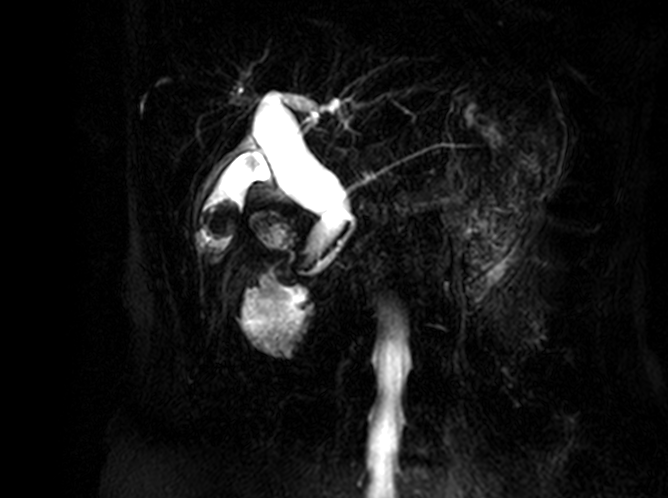

醫師懷疑不只是結石那麼單純,轉至本中心做MRCP(磁振膽胰管攝影)。

影像顯示:整個總膽管呈現紡錘狀擴張,符合「先天性總膽管囊腫」(成人型,Type I)。這種情況在成人很少見,100個人裡大概只有10-20個會出現症狀,常見的是腹痛、黃疸,或反覆膽管發炎。更重要的是,這類囊腫長久下來,發生膽管癌的機率比一般人高10-20倍。林女士目前沒有急性發炎,目前先用藥物控制症狀,每6個月回來做一次核磁共振追蹤,暫時不需要開刀。她說:「現在知道是什麼問題,內心平靜多了。」